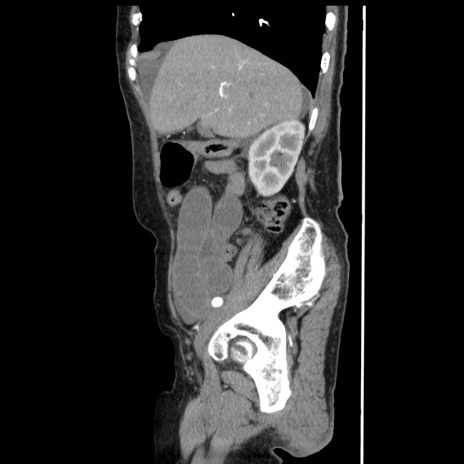

冠状断像

【症例】80歳代女性

【主訴】腹痛

【現病歴】8時間前から腹痛あり来院。

【既往歴】糖尿病、脂質異常症、子宮体癌にて子宮全摘術

【身体所見】意識清明・会話良好だが腹痛で苦悶様、全腹部にわたって反跳痛と圧痛あり

【データ】WBC 13600、CRP 0.14、LDH 224、CK 90